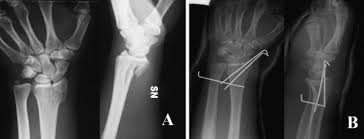

Paziente: donna, età 30 anni

Diagnosi: esiti di frattura articolare radio distale sinistro.

Frattura marginale volare trattata in gesso e viziosamente consolidata.

All’esame clinico, a 6 mesi dal trauma, deficit completo della flessione e parziale dell’estensione.

Situazione Pre Operatoria

a 6 mesi dal trauma, deficit completo della flessione parziale deficit dell'estensione

| Controllo radiografico medio/laterale prima dell'intervento |